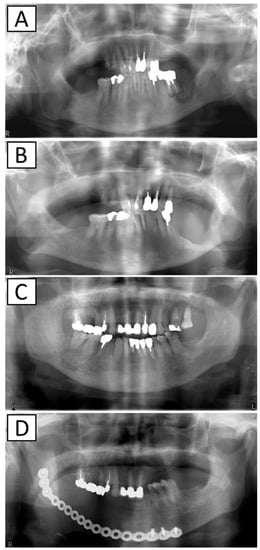

2.1. Impact of AR Drug Holidays on Treatment Outcomes

Figure 1. X-ray images before and after surgery. (A): Before marginal mandibulectomy, (B): after marginal mandibulectomy, (C): before segmental mandibulectomy, and (D): after segmental mandibulectomy.